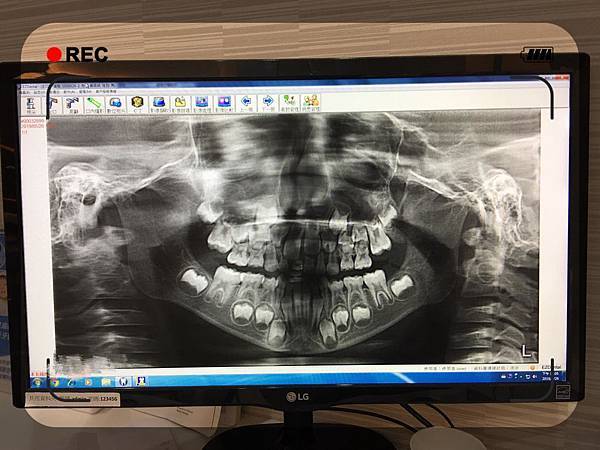

診所很細心,一開始就先幫嘟寶拍牙齒的X光片

媽咪第一次看到恆牙胚,還問護士:這是還未長出來的牙齒對嗎?

(謎之聲: 我們小時候不會去拍,所以沒看過也是正常的,哈哈)

一直以來都很困惑嘟寶的乳牙排列的整齊又漂亮

為什麼恆牙長出來卻是歪的,且生長速度很慢???

醫生說嘟寶的恆齒一顆的大小抵兩個乳牙位置

生長空間不足,就會冒得比較慢且長歪的...

牙齒的寬度大致是固定的,但長度還會隨著年齡增長而變長,

等恆齒全部長好之後再觀察是否要矯正齒列!!